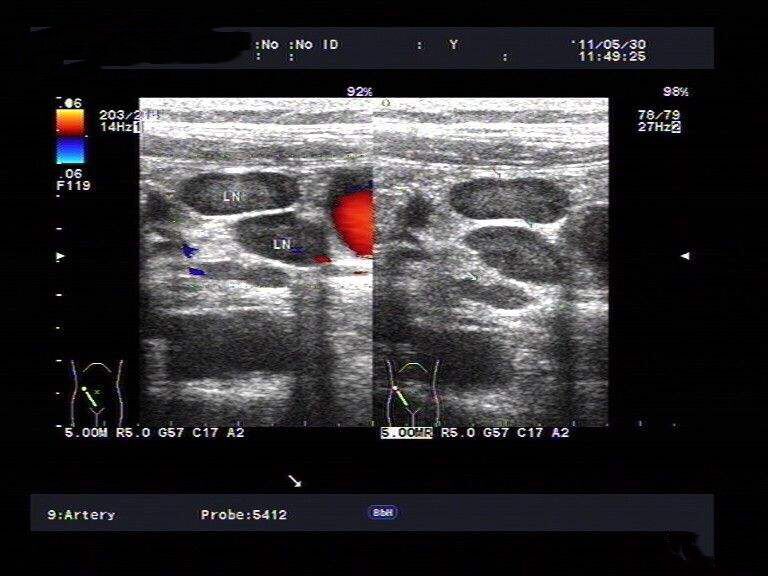

3、小器官:眼睛、甲状腺、乳腺、颈部、四肢、躯干、体表软组织疾病的超声检查。

彩色多普勒超声对心脏及血管病变的诊断:

彩色多普勒超声能够同时评价血管的二维结构和实时血流动力学变化。我院超声科已开展此项技术。

2、随着生活条件的改善和老龄人口的增多,血管病变的发生率逐年上升。多普勒超声诊断血管疾病既可观察到血管形态,结构,病变的范围,又能实时和动态检测血流动力学情况;且检查具安全,无创,廉价等特点,超声已逐渐成为血管病变的******检查方法。